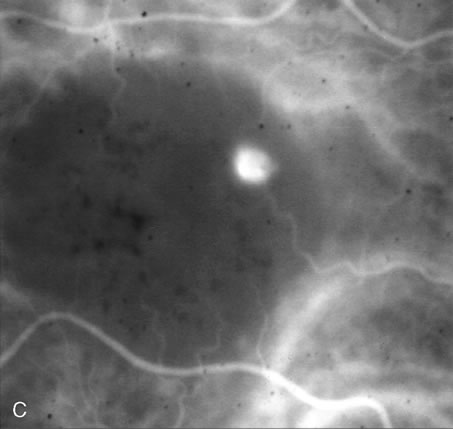

FA is also useful in characterizing two other subgroups of CNV: retinal angiomatous proliferation (RAP)8–16 and polypoidal choroidal vasculopathy (PCV).17–50 RAP begins in the deep retinal complex, forming intraretinal neovascularization (IRN), which may subsequently progress to extend beneath the neurosensory retina, forming subretinal neovascularization (SRN), and a vascularized PED.8 In the later phases of the process there may be a retinal-choroidal anastomosis (RCA). Clinical features of RAP include intraretinal hemorrhages, cystoid macular edema, and associated vascularized PED. FA is useful in revealing the presence of the angiomatous intraretinal vascular complex and the extension of the associated PED (Figs. 12 and 13). However, other diagnostic techniques such as indocyanine green (ICG) angiography, and optical coherence tomography (OCT) may be able to better demonstrate the presence of the RAP lesion.

Fig. 12. A. Clinical photograph of a retinal angiomatous proliferation (RAP) lesion (arrow). Note the intraretinal angiomatous proliferation, a feeding retinal arteriole, and a draining retinal venule, as well as the presence of intraretinal hemorrhages. B–C. Fluorescein angiography reveals late leakage from the RAP lesion.